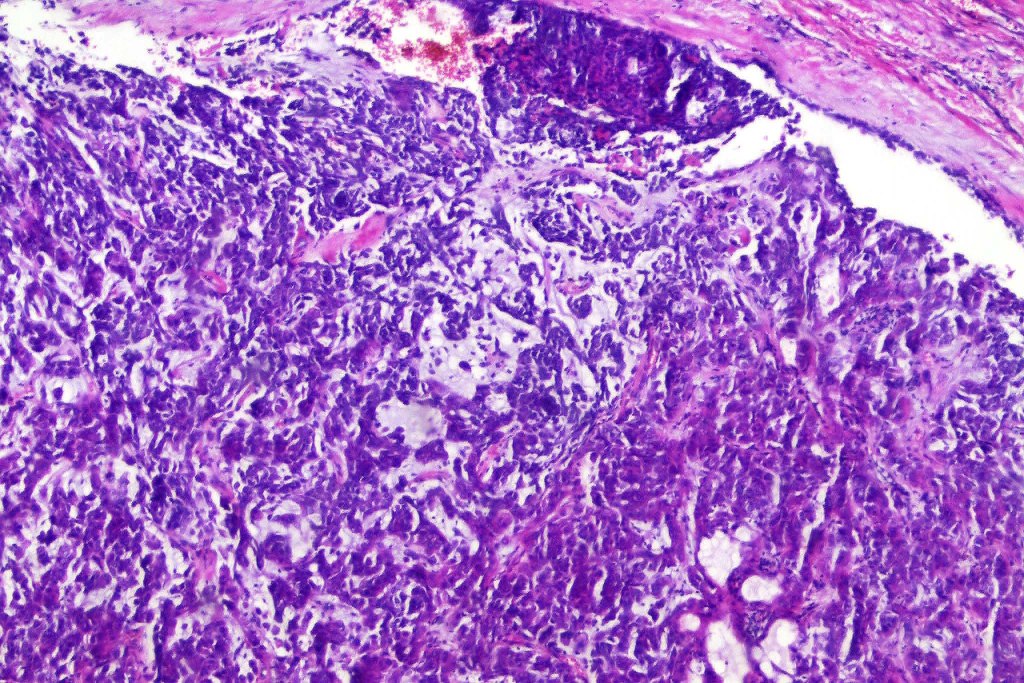

•Infiltrative growth pattern

•Nuclear pleomorphism, prominent nucleoli

•Marked mitotic activity

•Abnormal mitoses

•Lymphovascular invasion